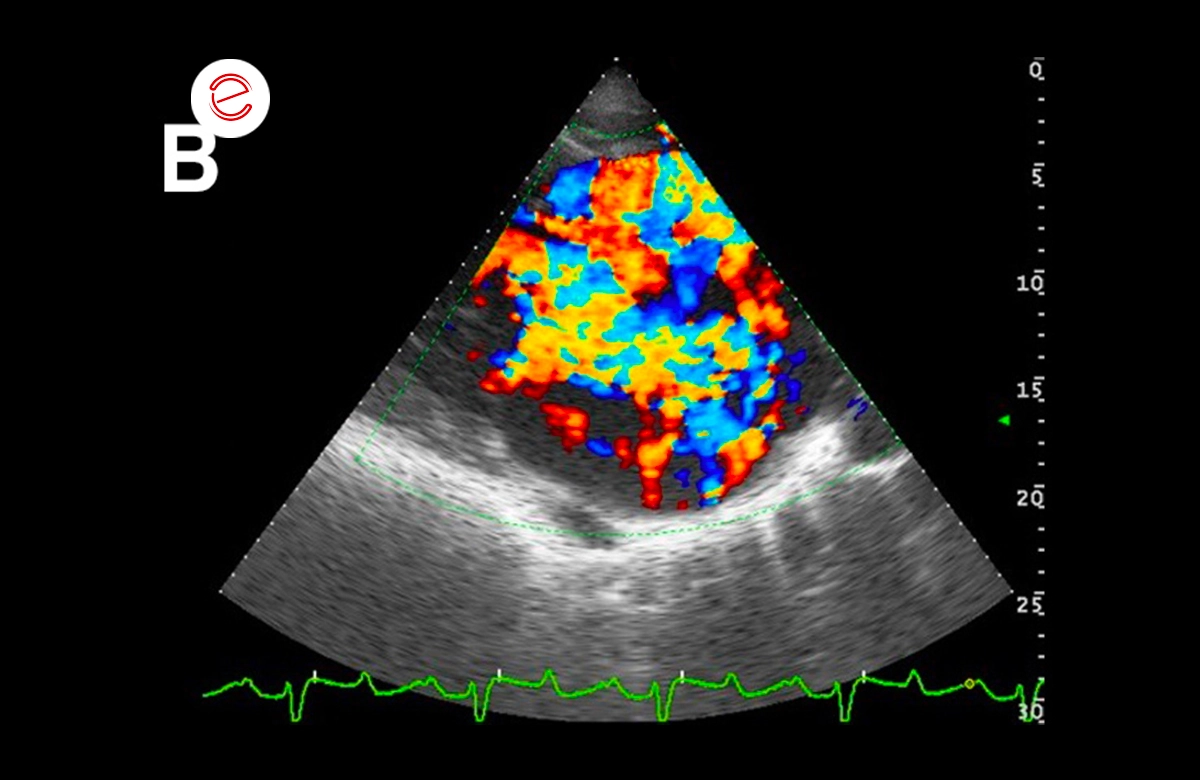

These images show: A) severe aortic regurgitation jet, B) severe mitral regurgitation jet; C) mild pulmonary regurgitation jet.